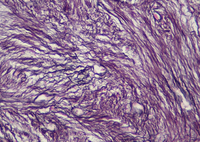

• NRBC

Najmaldin Saki, P...

Nucleated Red Blo...